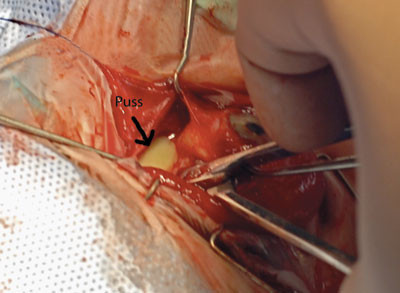

Pasienten ble operert samme kveld. Den periorbitale abscessen ble tømt, og det ble sydd fast et bølgedren. Det ble deretter gjort bilateral åpning av fremre etmoidalsinus og antrostomi til maxillarsinus. Vi fant store mengder puss i alle sinuser. Dyrkning av bakterieundersøkelse fra lokalsykehus viste oppvekst av anaerobe staver.